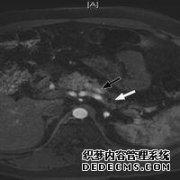

全部展开 在胰腺病变中,胰管扩张的程度各不相同。 超过95%的胰头癌病例有不同程度的胰管扩张。 对于慢性胰腺炎,胰管扩张为...